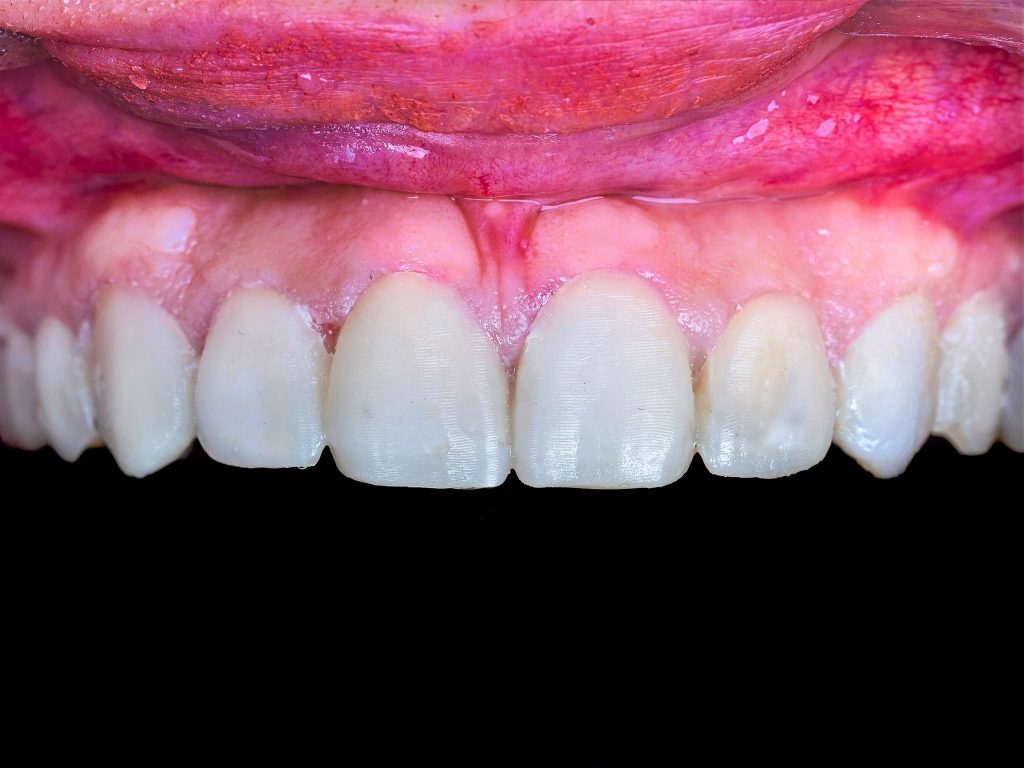

The case presented in this case report is for a 27-years-old female patient with a chief complaint of aesthetic correction for her smile. The patient was unhappy with her smile. After clinical examination, there were previous old composite veneering done poorly and incorrectly to close the multiple interdental spacing. After discussing the various treatment options (i.e., orthodontic treatment, direct, or indirect veneers), indirect ceramic veneering was selected. The step-by-step treatment protocol is presented in the images below.